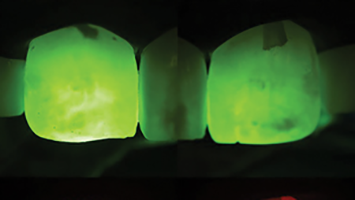

The loss of a tooth can be a stressful event for any individual. Upon learning that a tooth in the esthetic zone has been lost, or is going to be extracted, a patient’s immediate statement is almost always: “I don’t want to lose a tooth!” followed by the question: If that’s going to happen, how do … Read more